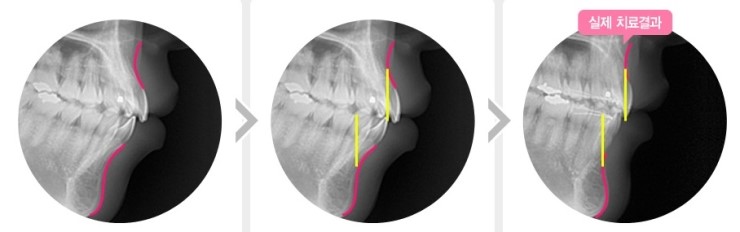

▼ 일반 돌출입 교정 ▼

▼ 스피드 돌출입 교정 ▼

스피드 돌출입 교정 치료 순서 및 효과

스피드 돌출입교정 : 공간폐쇄단계(돌출입해서) -> 치아배열+마무리 단계

일반 돌출입교정 : 치아배열단계 -> 공간폐쇄단계(돌출입 해소) -> 마무리단계

스피드 돌출입교정은 일반 돌출입교정과는 다르게

발치를 통해 공간을 확보하여

먼저 입을 넣고 예뻐진 후 치열을 맞추는 단계와 마무리 단계를 함께하여

먼저 예뻐지고 교정시간이 3~6개월 단축 되어

교정을 시작하면서 바로 예뻐진 얼굴을 볼 수 있습니다.